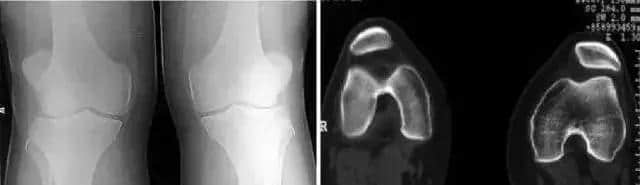

1 髌骨半脱位

最多见于十几岁的女孩和年轻妇女,发作性的膝关节打软,Q角增大 (>15°)。髌骨恐惧试验 (Patellar apprehension sign)阳性。轻度积液,中、重度积液说明有关节内血肿,提示髌骨脱位伴骨软骨骨折和出血。